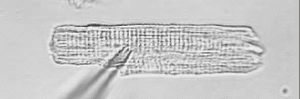

本研究室の研究では,特に実用的に応用できる研究を目標にしています.具体的には,医療現場で,医師が経験に基づいた診療を行う際に疑問に思うこと,判断に迷う状況などについて,シミュレーションモデルを使った解析を行うことで,経験則に理由を付けられるようなテーマを目指しています.

このようなことから,医学部や病院の医師との共同研究が多く,実際の臨床で使われるデータに基づいたシミュレーションモデルの構築や解析なども行っています.また,卒業生は,生命科学の知識と,研究室で身に着くソフトウエアの技術を生かして,医療機器メーカーなどへの就職が多いです.

野間昭典先生が長年作られてきた,心筋細胞や心臓に関する生理学的なメカニズムを再現する数理モデルを中心に,心筋細胞や心臓の生理学を数理的に理解する電子教科書が出版されました.現在,基礎編と応用編が完成しています.教科書は,丸善より DVD として出版されています.下記ページより購入が可能です.